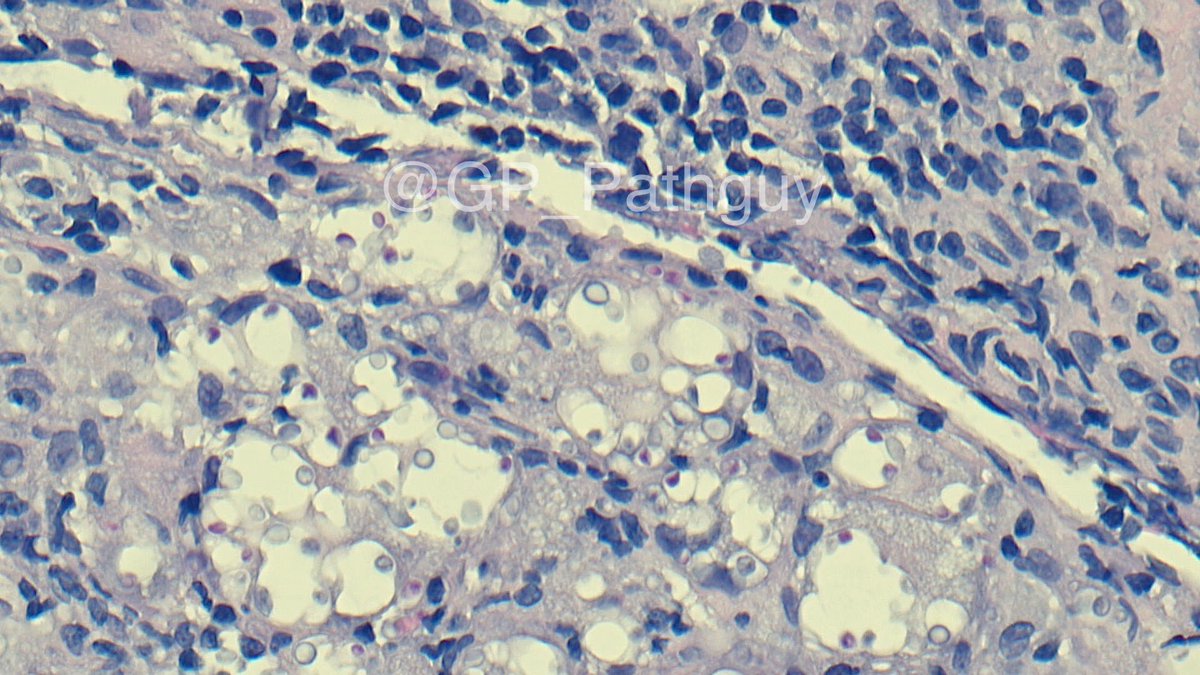

Schistosoma haematobium in a high-grade urothelial carcinoma resection. Weirdly present in the ureters and seminiferous tubules as well. Critters are among us. @UTHSC_ID @natesumMRSA